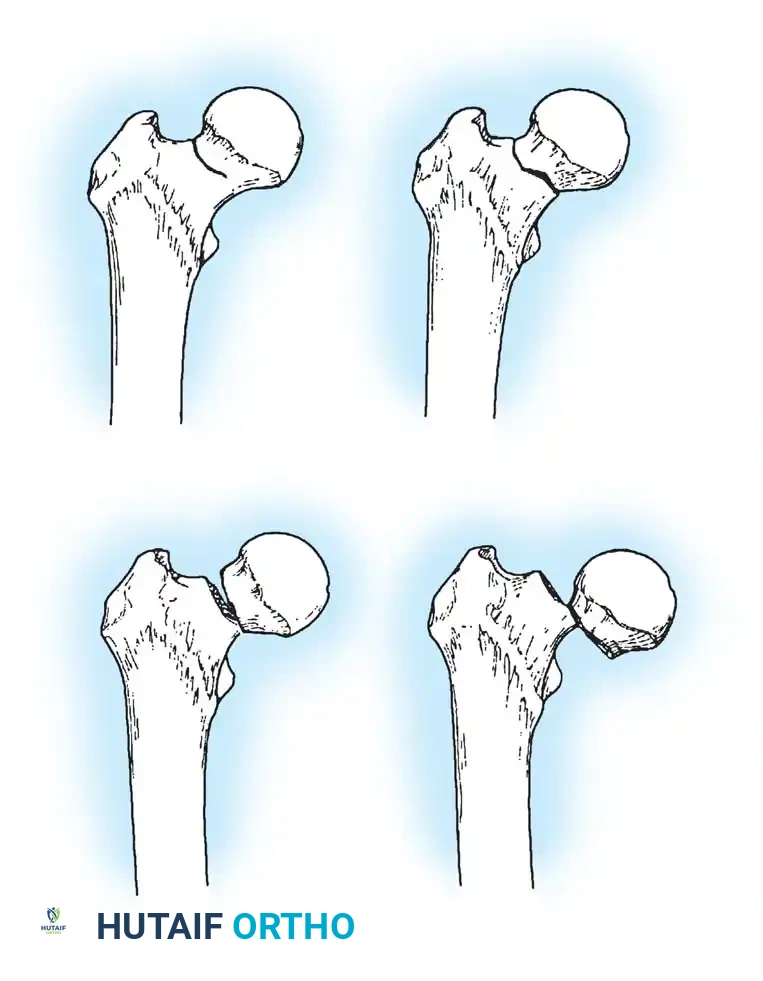

Fig. 52-2: Boyd and Griffin Classification of trochanteric fractures. Types 1 and 2 represent relatively simple patterns, while Types 3 and 4 involve subtrochanteric extension and multi-planar comminution.

- Type 1: Non-comminuted fractures extending along the intertrochanteric line. Simple to reduce and highly stable.

- Type 2: Comminuted fractures along the intertrochanteric line. Reduction is more challenging due to cortical comminution.

- Type 3: Fractures with a subtrochanteric extension. These are inherently unstable and difficult to manage.

- Type 4: Complex fractures involving the trochanteric region and proximal shaft in at least two planes (sagittal and coronal).